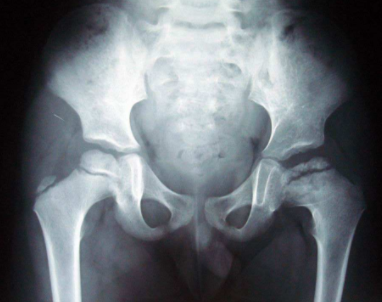

二期股骨头坏死是怎么回事?郑州骨科病医院告诉你应

郑州骨科病医院介绍在临床中出现了二期股骨头坏死的疾病情况,属于相对比较严重的情况。如…[详情]